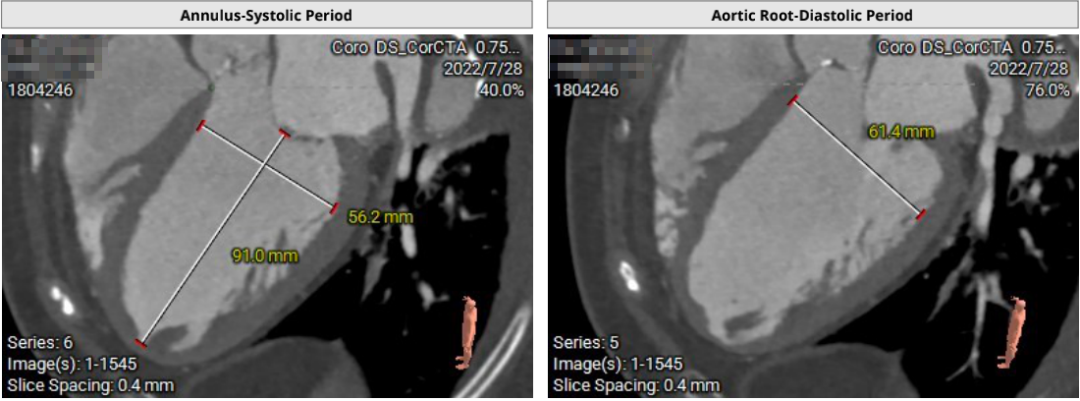

患者71岁女性,诊断为主动脉瓣重度狭窄合并心功能不全,瓣口面积仅0.5cm²,跨瓣压差超过50mmHg,且EF仅27%,心功能极差。术前CT检查瓣环周长72.2mm,LVOT呈喇叭型。CT检查同时发现患者入路血管狭窄,股动脉直径5.3cm,锁骨下和颈内动脉直径都小于5.0cm,对操作造成了一定困难。

患者64岁男性,Type 0 型二叶瓣、横位心。主动脉瓣中度狭窄,重度反流,瓣环周长92.0mm,平均径29.0mm。LVOT周长98.7mm,升主扩张,窦部结构极限,锚定能力极限。入路两侧血管轻度迂曲,分叉高度可,两侧血管内径均>8mm。

患者左、右冠高度,瓣叶长度,窦宽相对瓣膜均尚可,冠脉风险低。但由于患者重度AR,可能因植入深度和选择大型号瓣膜,带来较高的传导阻滞风险。其次,患者升主扩张,存在破裂风险。最后,患者是横位心,瓣环及流出道结构大,术中瓣膜释放的位置达到了极限,瓣膜释放后可能会发生位移,有瓣中瓣风险。

首先,最重要的是观察瓣环结构,理论上如果瓣环周长超过85mm,尽量就不做;第二,看流出道情况,最好是直筒状的,瓣环和瓣下4mm的直径比值,理论上不能超过1:1.1,如果超过1.1以上就变成喇叭状,也不建议做;第三,避免存在升主动脉显著扩张,如果扩张明显,无法提供有效的锚定。总体来说,最主要的一定是瓣环直径,瓣叶有没有增厚,瓣叶有没有钙化,瓣环能否有效固定住植入的瓣膜。瓣环的固定和锚定条件,是反流患者能否进行TAVR的决定因素。